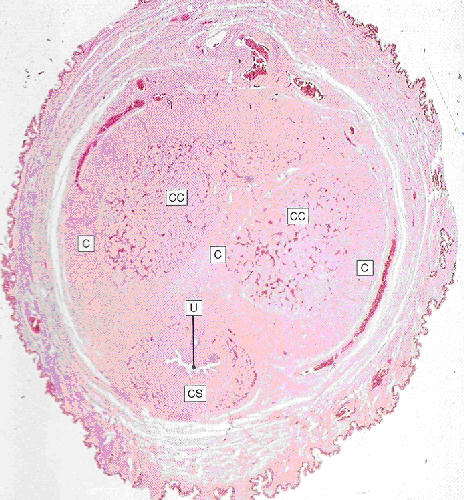

Cross section through the penis

CC: Corpora cavernosa

CS: Corpus spongiosum

U: Urethra

C: Fibrocollagenous capsule

Source: Stevens and Lowe Fig 17.19 (p 318)